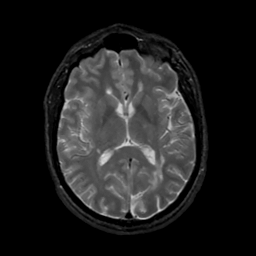

MR Study #4, March 3, 1991 -- Slice #27

[Home][Help][Clinical][Tour 1][Tour 2] Slice 27